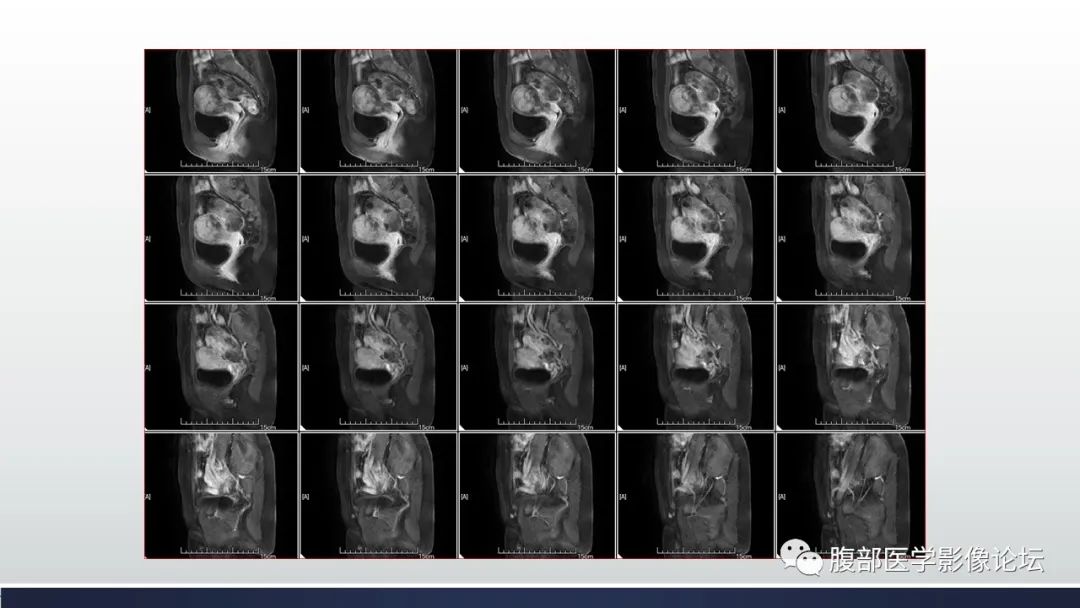

【病例】子宫内膜透明细胞癌1例MR-5

【病例】子宫内膜透明细胞癌1例MR-6

【病例】子宫内膜透明细胞癌1例MR-7

【病例】子宫内膜透明细胞癌1例MR-8